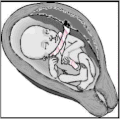

A nuchal cord is when the umbilical cord becomes wrapped around the fetus's neck.[1] Symptoms present in the baby shortly after birth from a prior nuchal cord may include duskiness of face, facial petechia, and bleeding in the whites of the eye.[1] Complications can include meconium, respiratory distress, anemia, and stillbirth.[1] Multiple wraps are associated with greater risk.[3]